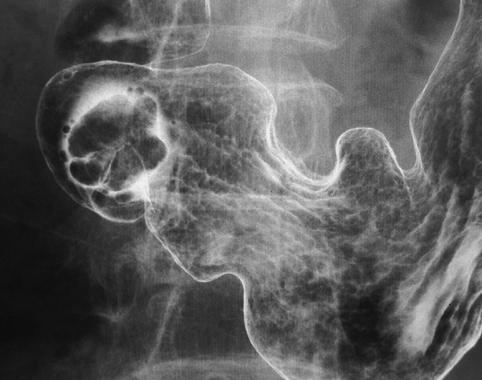

질환(병리주체)의 분류 악성 상피성종양/선암

부위(장기별) 위(부위)/전정

검사방법 X-P

종양의 육안분류 0형(표재형)/I형(I)

종양의 최대경(밀리미터) 20~24

종양의 심달도 m